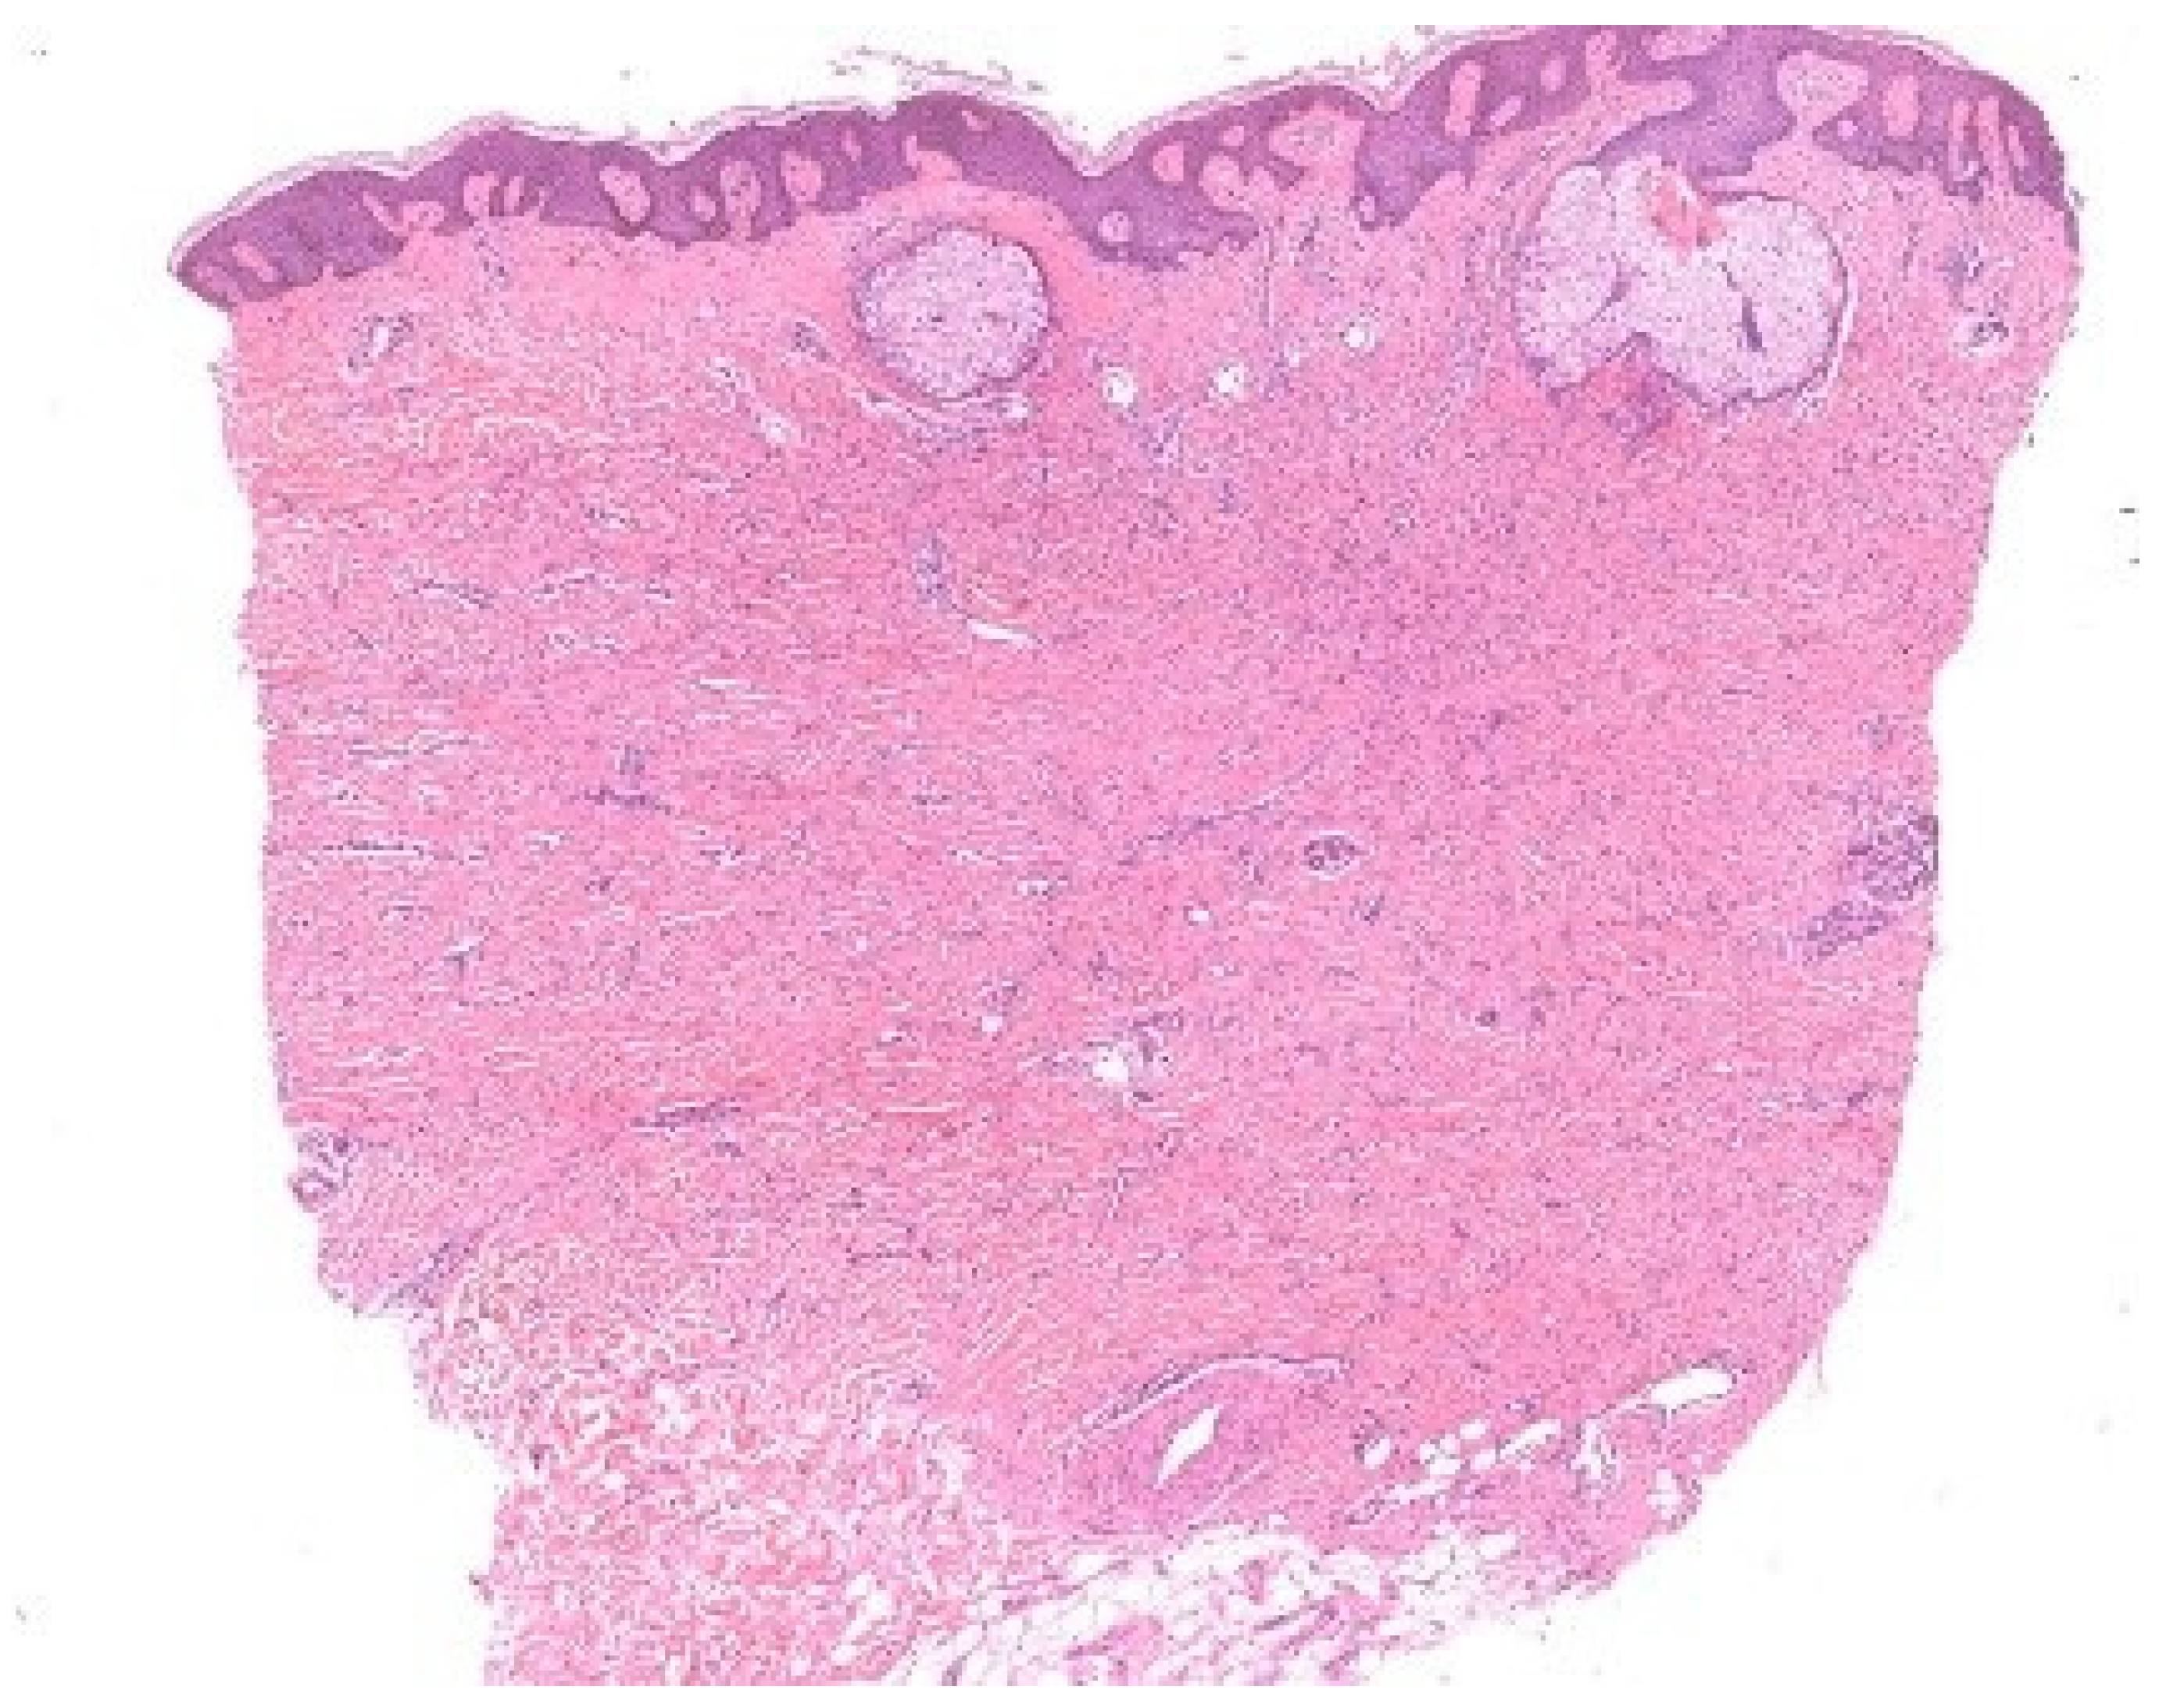

Böer demonstrated that unconscious perceptual rules, particularly figure–ground segregation, govern what is consciously noticed under the microscope [8]. This process allows us to isolate figures against a background but can also mislead: the fibroblast proliferation of a dermatofibroma is readily detected by an expert, while a novice may be distracted by incidental sebaceous induction and overlook the true lesion (Figure 6). Likewise, subconscious mechanisms of visual perception may cause interstitial infiltrates—especially when sparse—to receive less attention than epidermal, perivascular, or perifollicular infiltrates [9].

Figure 6.

Figure–ground segregation. In this dermatofibroma with sebaceous gland induction, the round, simple structures of the sebaceous glands contend with the ill-defined proliferation of fibroblasts in the dermis, which lacks a continuous contour.

These observations resonate with the notion of semi-encapsulated perception argued by Raftopoulos [10] and with Magnani’s eco-cognitive model of abduction [3]. Early visual processing remains cognitively independent, but later stages integrate knowledge. Novices attend to simple figures, while experts exploit tacit knowledge to prioritize ground features. Still, expertise does not abolish error: dermatofibrosarcoma protuberans can be mistaken for dermatofibroma when unconscious biases prompt premature closure. Böer’s studies underscore that unconscious processes are constitutive of abductive reasoning but are also sources of diagnostic pitfalls. Training that enforces systematic scrutiny of “ground” details can counteract these biases and refine abductive precision.